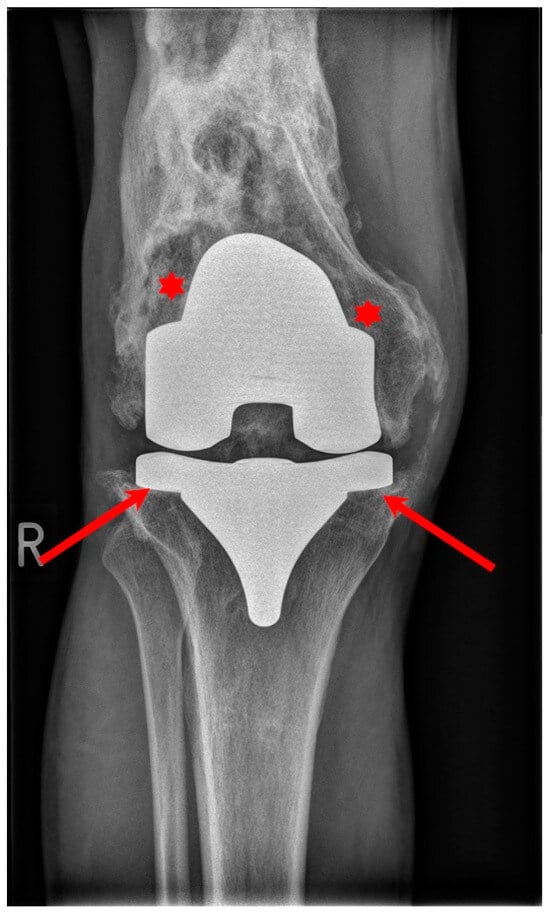

4. Cementless Knee Replacement

5. Discussion